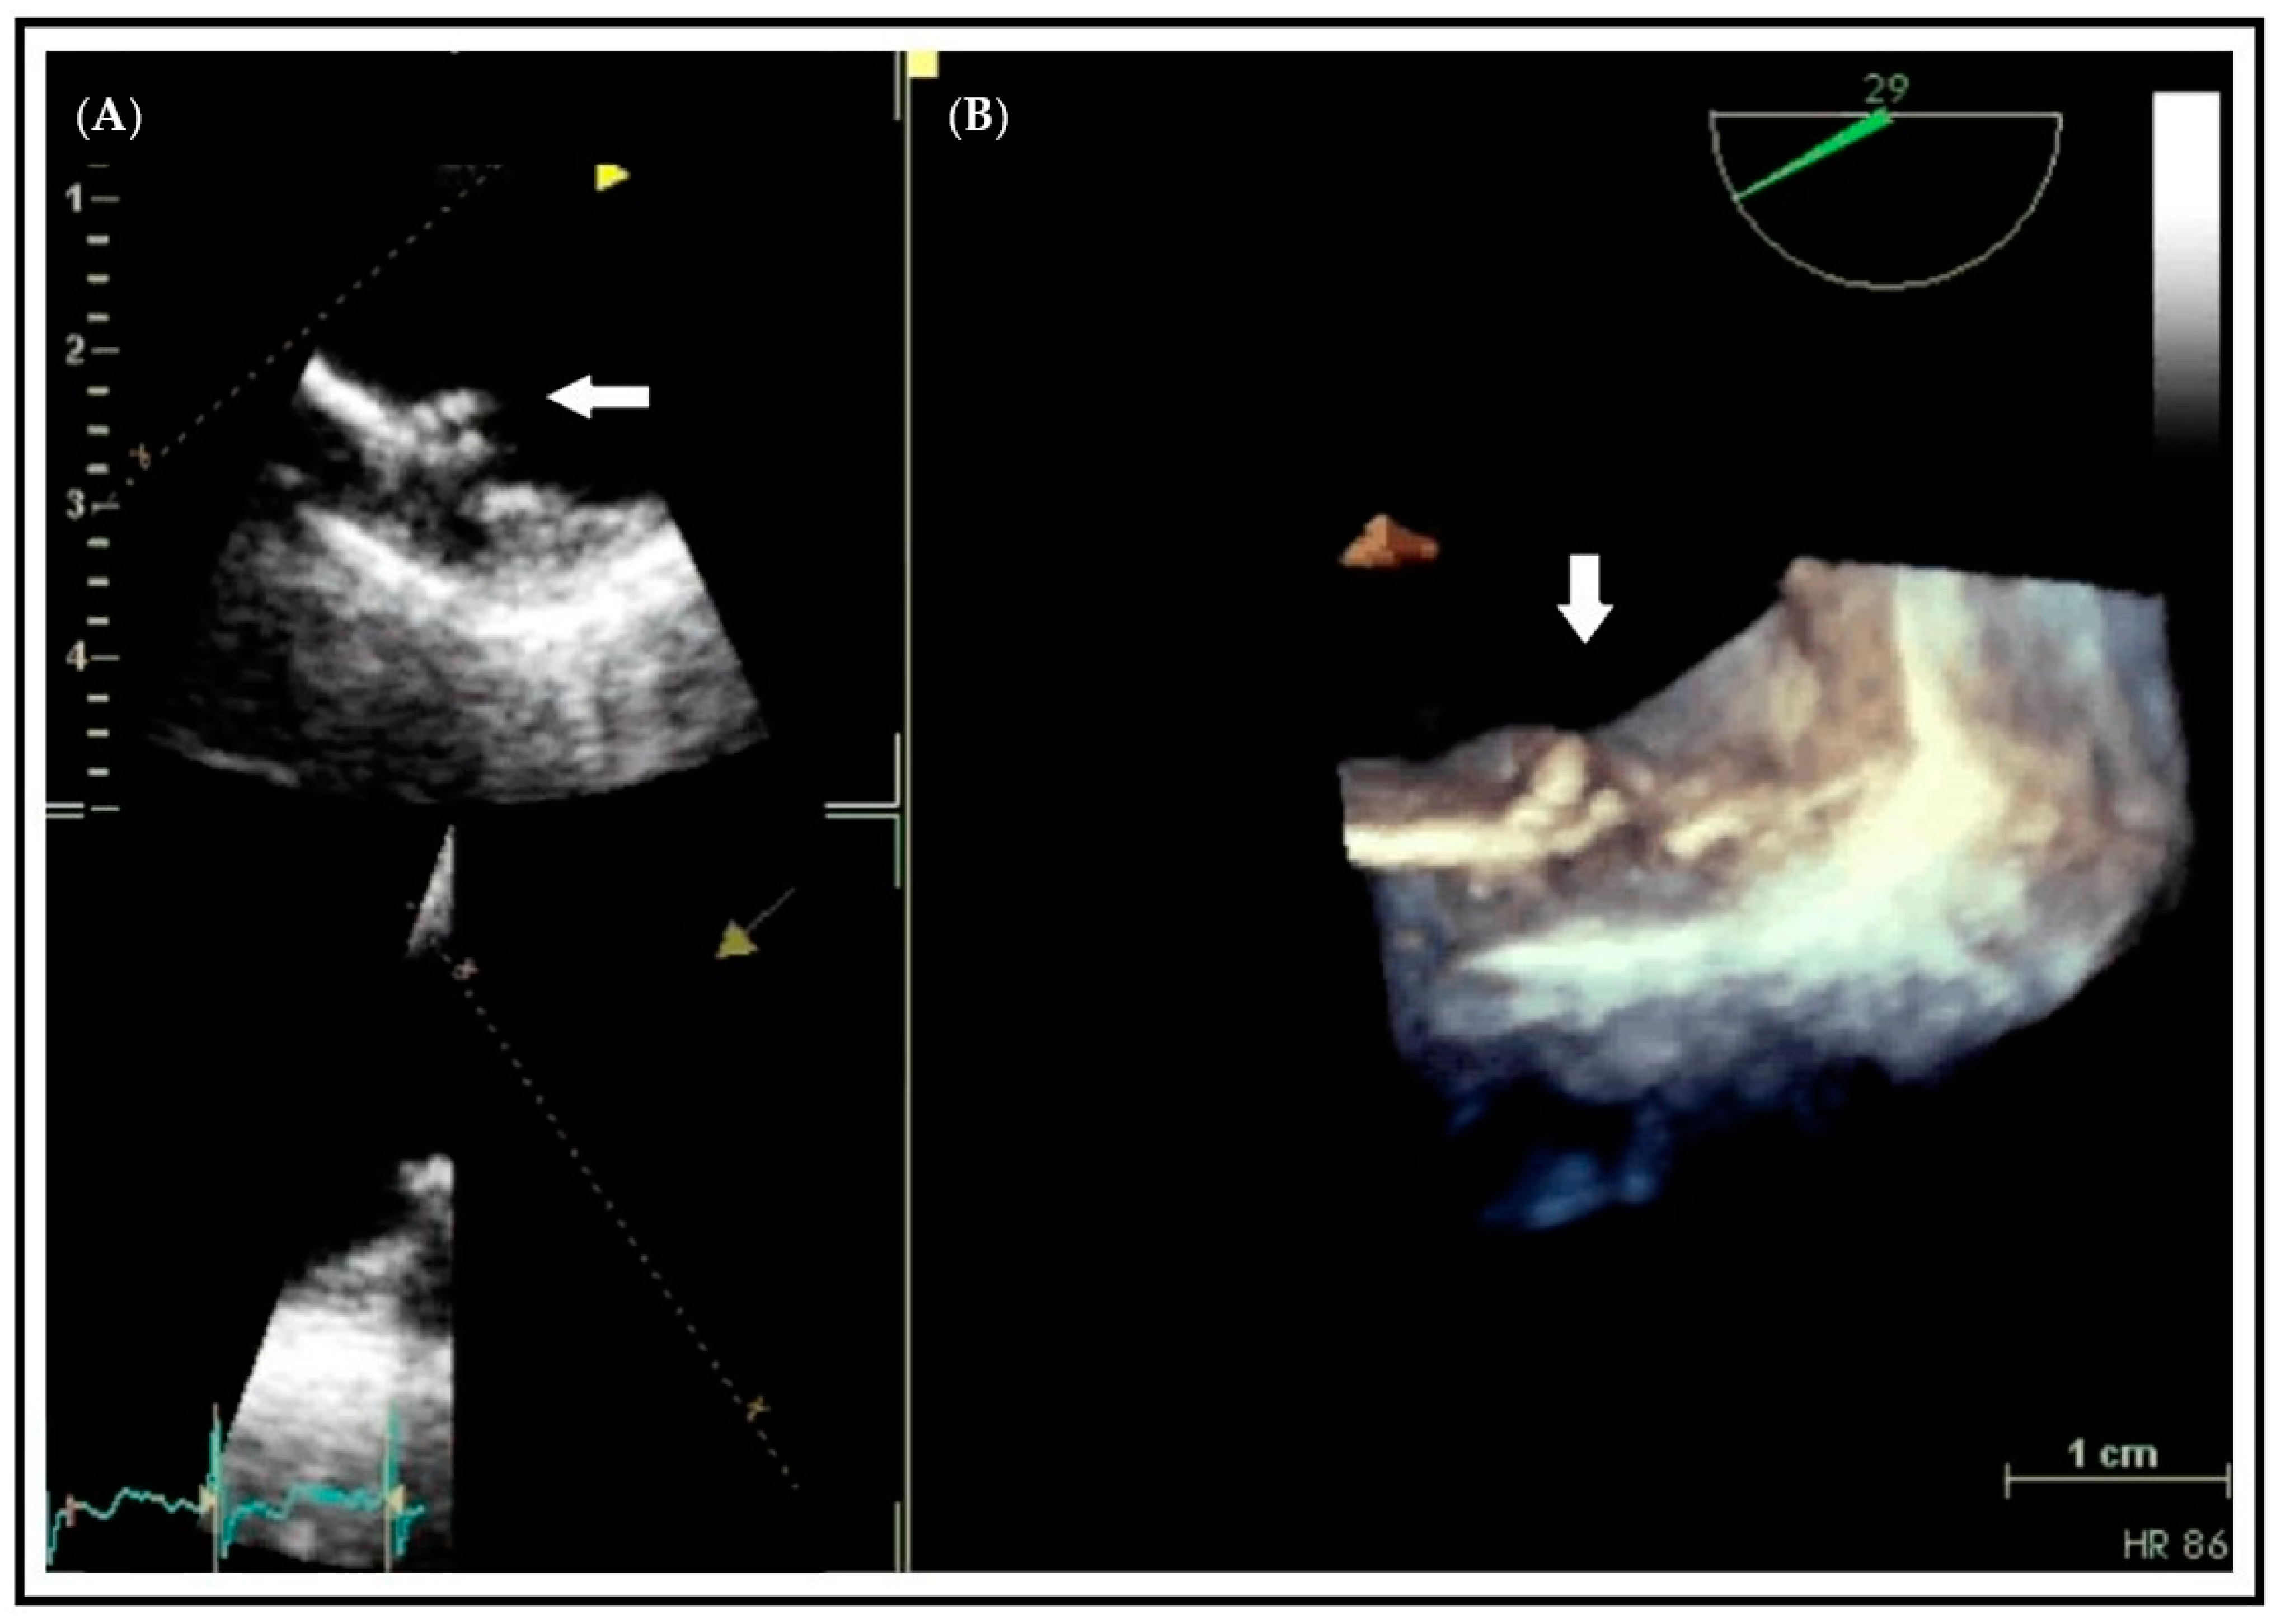

- Weissler-Snir, A.; Greenberg, G.; Shapira, Y.; Weisenberg, D.; Monakier, D.; Nevzorov, R.; Sagie, A.; Vaturi, M. Transoesophageal echocardiography of aortic atherosclerosis: The additive value of three-dimensional over two-dimensional imaging. Eur. Heart J. Cardiovasc. Imaging 2015. [Google Scholar] [CrossRef]